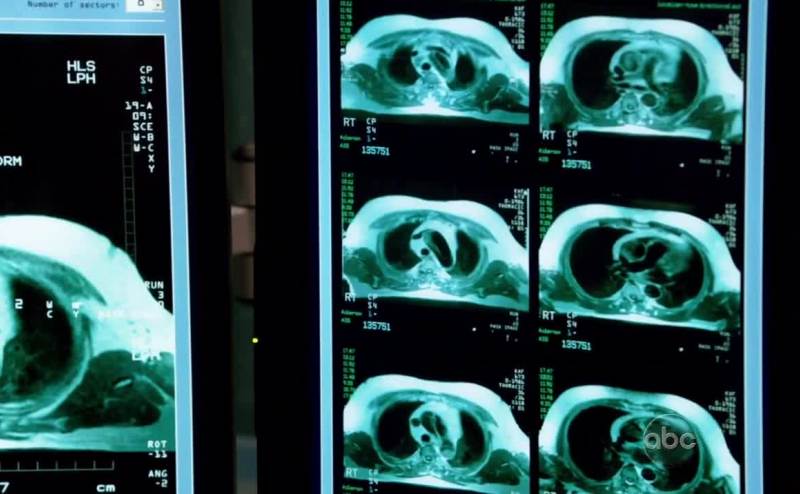

Let's get him in the scanner.

带他去做CT

It's like a hole. He probably injured it

洞状裂痕 可能是他小时候